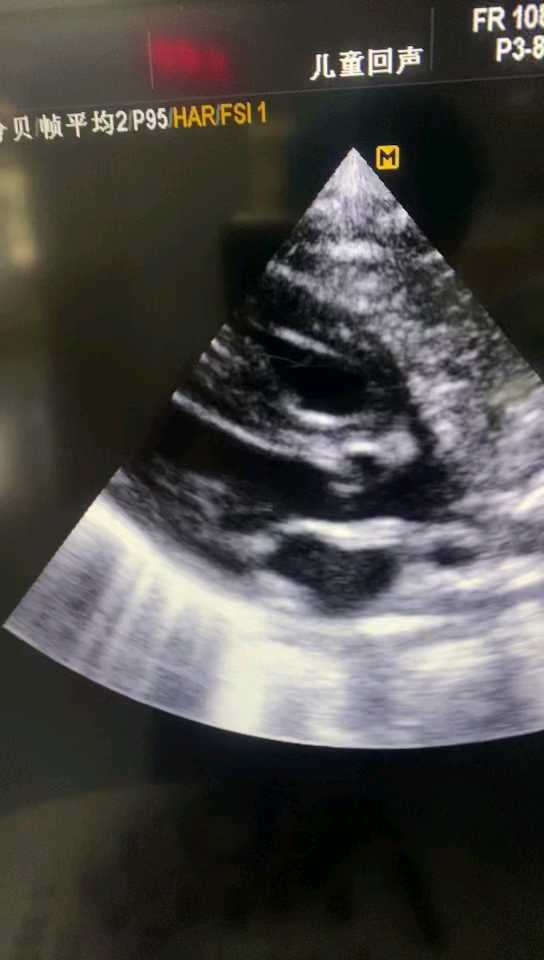

来自同行的“钟艳lin"的病例:足月,未产检,因胎儿窘迫剖宫术,有诊断窒息,气管插管有吸到胎粪,上机后血氧维持尚可。血压低,有生理盐水扩容2次,10ml/kg,心脏彩超提示室间隔肥厚,右心肥厚,左心充盈欠佳,左右心房不大,pda双向分流,无三尖瓣反流,卵圆孔1.6mm。扩容后下腔静脉4.2mm。

使用肾上腺素心率加快,后改用去甲肾上腺素,一天后,心脏彩超提示左心充盈有好转,右心肥厚仍存在,不存在SAM…

从慢放的镜头来看,前瓣靠拢室间隔发生在收缩后期或舒张早期,而不是收缩中期,此时左室已经排空,并不存在导致血排不出去,没有事实上左输出道梗阻表现。另一方面左室几乎排空也可以说明左室收缩功能良好或者亢进…。虽然没有输出道梗阻sam,但强心应该也没有任何意义,因为收缩时左心室几乎已经排空。经过去甲补液等治疗,左室充盈在好转!